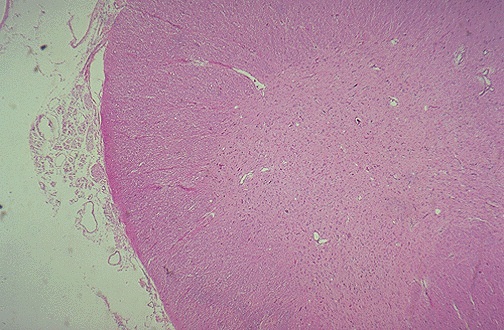

There is loss of anterior horn cells apparent in this H and E stained section of spinal cord in this microscopic section in a case of ALS.